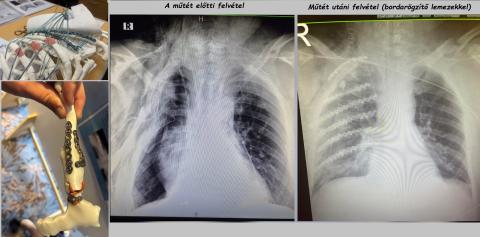

Bordarögzítő lemez

A megfelelően kiválasztott, időben elvégzett műtéti stabilizálás:

• csökkentheti az intenzív osztályos kezelés időtartamát,

• lerövidítheti – vagy akár megelőzheti – a gépi lélegeztetés szükségességét,

• csökkentheti a kórházi tartózkodás idejét,

• gyorsabb visszatérést tehet lehetővé a megszokott életvitelhez.